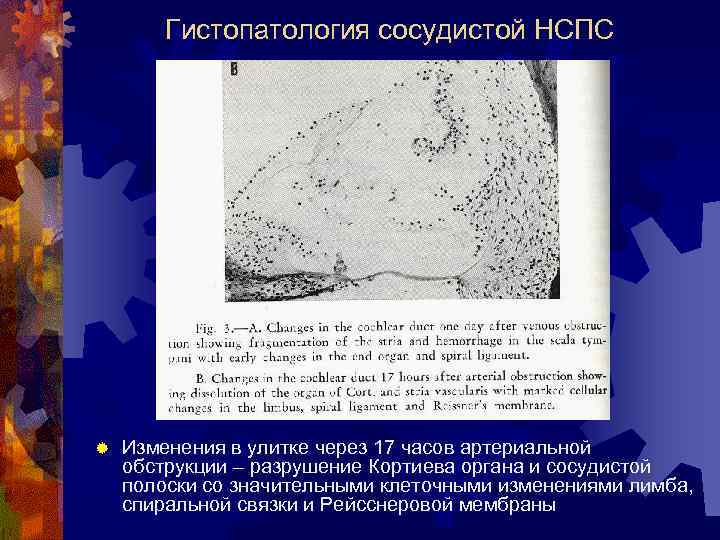

Гистопатология сосудистой НСПС ® Изменения в улитке через 17 часов артериальной обструкции – разрушение Кортиева органа и сосудистой полоски со значительными клеточными изменениями лимба, спиральной связки и Рейсснеровой мембраны